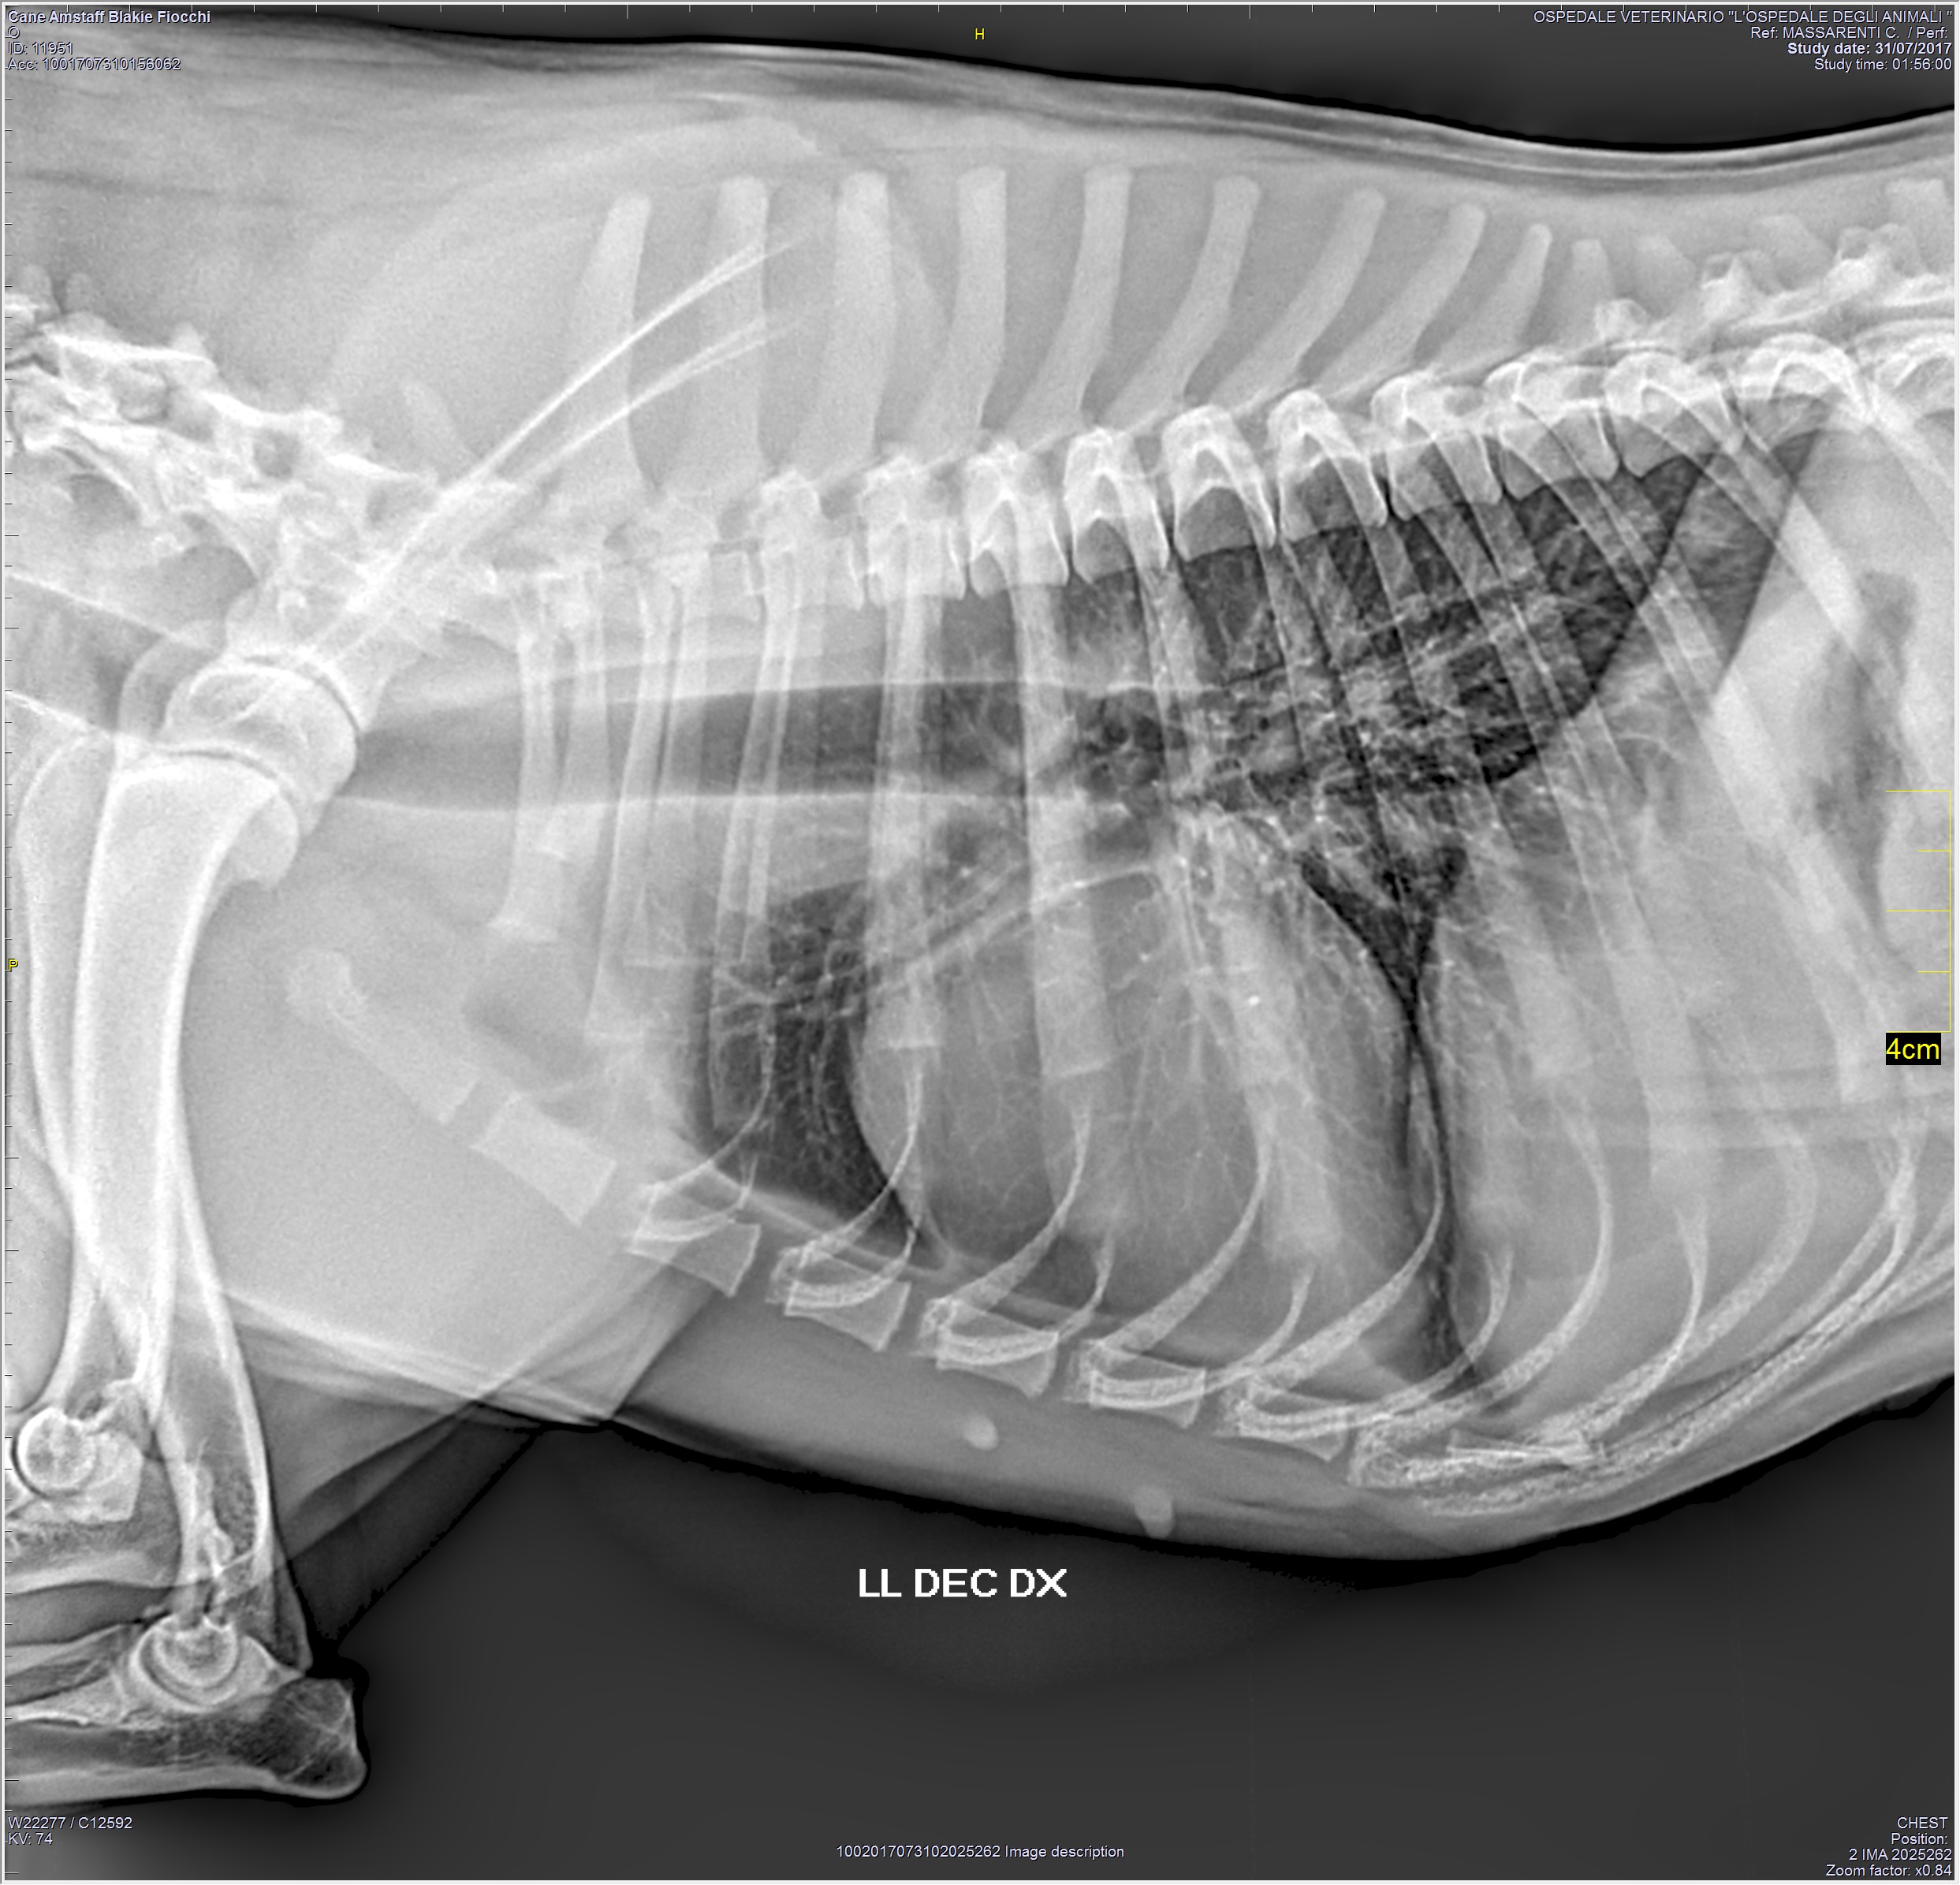

RADIOLOGIA

La radiologia veterinaria è una branca della diagnostica per immagini che utilizza i raggi-x per la valutazione delle diverse strutture anatomiche. L' Ospedale degli Animali dispone di un apparecchio radiologico digitale diretto, che permette di ottenere rapidamente radiografie di altissima qualità ed è in grado di eseguire studi radiografici di routine e d'urgenza, 24 ore su 24.

L'Ospedale degli Animali è abilitato ad eseguire studi radiografici specifici per le patologie congenite di anche e gomiti, ai fini della valutazione FSA.

Al termine dell'esame le immagini vengono digitalizzate su un cd-rom che resta a disposizione del proprietario o inviate al suo indirizzo e-mail.